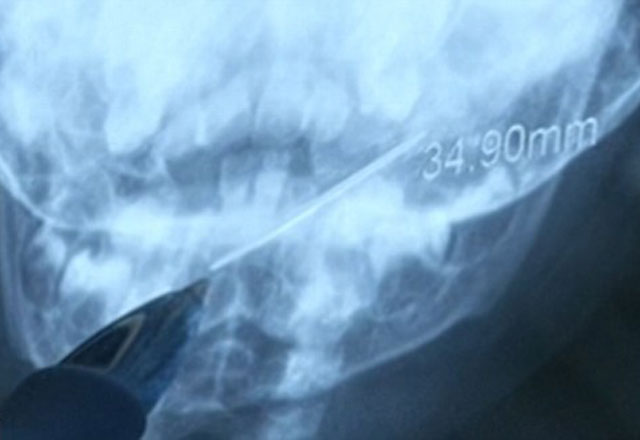

Röntgeni Gören Doktor Anne - Babaya Saldırdı... Çin'de iğne yutan 1 yaşındaki bebek acilen hastaneye getirildi, bebeğin boğazına takılan iğne 4 cm olarak ölçüldü.Daily Mail'de yayınlanan habere göre, Çin'de 1 yaşındaki bebek 4 cm'lik iğne yuttu.

Xi'an adındaki bebek metali yuttuktan saatler sonra hastaneye yetiştirildi.4 cm'lik iğnenin bir ucu bademciklerine değerken diğer ucu gırtlağındaydı. Acilen çıkarılmazsa iç kanamaya veya enfeksiyona neden olabilirdi.